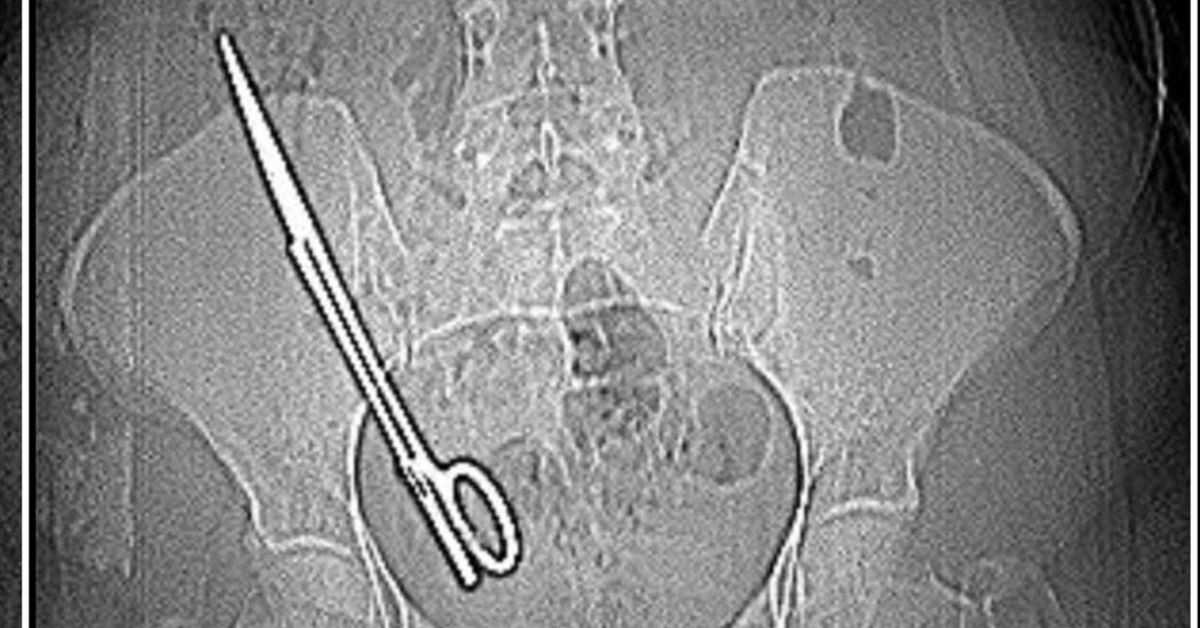

Ameliyatta karnında unutulan makas, 7 yıl sonra baş ağrısıyla ortaya çıktı

İddiaya göre; Koray Ş., 7 yıl önceki ameliyattan dolayı bir komplikasyon oluştuğunu ve acilen ameliyat etmesi gerektiğini söyledi. Doktorun tavırlarından şüphelenen Fatma Kala, ameliyat olmayı reddedip KSÜ Sağlık Uygulama ve Araştırma Hastanesi’ne gitti. Burada yapılan tetkiklerde Kala’nın karnında 16 santimetre uzunluğunda makas olduğu tespit edildi. Ameliyatla karnındaki makas çıkarılıp sağlığına kavuşan Fatma Kala, hastaneden çıktıktan sonra avukatı aracılığıyla 7 yıl önce ameliyatı gerçekleştiren doktor Koray Ş. hakkında Kahramanmaraş Cumhuriyet Başsavcılığı’na suç duyurusunda bulundu.

Baş ağrısı şikayetiyle gittiği hastanede doktorların ‘Karnında makas var’ deyince şoke olduğunu belirten Fatma Kala, 2017 yılında kist ameliyatı olduktan sonra iç kanama geçirdiğini ve tekrar ameliyata alındığını, makasın da o ameliyatta unutulduğunu söyledi. Karnında makas varken küçük çocuğu ile birçok defa MR odasına girdiğini belirten Kala, “Bundan 7 yıl önce özel bir hastanede ameliyat oldum. O günün gecesinde tekrar iç kanama geçiriyorum ve ikinci ameliyatımı oluyorum. Bu ameliyatta maalesef ameliyat olan bölgemde ameliyat makası unutuyorlar ve biz bunu 7 sonra öğreniyoruz. Baş ağrısından dolayı hastaneye gittik. Hastanede doktorumuz MR’a girmem gerektiğini söyledi. Ben MR teknisyenine daha önce çocukla beraber MR odasına girdiğimde benim sağ tarafımda çekme olduğunu söyledim.

Teknisyen bana ‘Bu şekilde seni MR’a alamam, çok tehlikeli. Acilen ameliyat olduğun doktoru bul’ dedi. Doktorumuz bizi hemen röntgene aldı. Röntgende bir yabancı cisim görmüş ama bize söylemedi, ‘Daha önceki ameliyatından dolayı bir komplikasyon oluşmuş. Seni ameliyat edip dedi o komplikasyonu ortadan kaldırmam gerekiyor’ dedi. Biz doktorun telaşlı tavrından şüphelendik. Eşimle birlikte tıp fakültesine gittik. Oradaki acil doktorlarına başımızdan geçen olayı anlattık. Onlar beni röntgene soktu. Oradan ilaçlı tomografiye girince daha önceki ameliyatımda bırakılan makas orada görüldü. Genel cerrahi bölümünde bu makas çıkarıldı” diye konuştu.